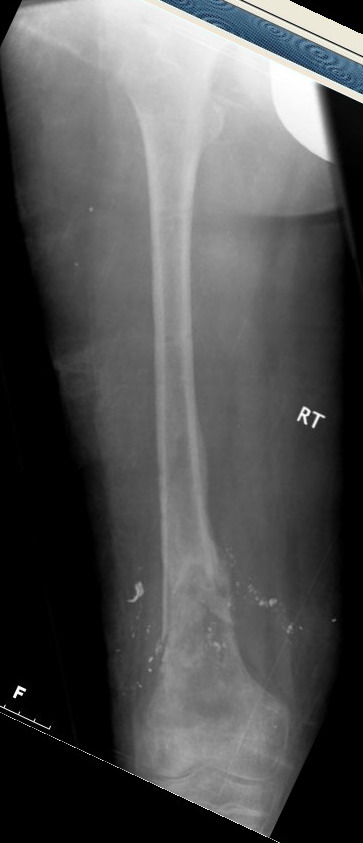

Выше представлены рентгенограммы открытого оскольчатого перелома нижней трети голени X-rays of Compound Comminuted # Distal/3 Lt Tibia

Операционные снимки перед и после наложения аппарата Илизарова In operation room before and after Ilizarov apparatus has been applied

Послеоперационные рентгенограммы Postoperative X-rays

В нижнем ряду представлены рентгенограммы после окончательной репозиции. And final reduction after Hexapod program has been finished